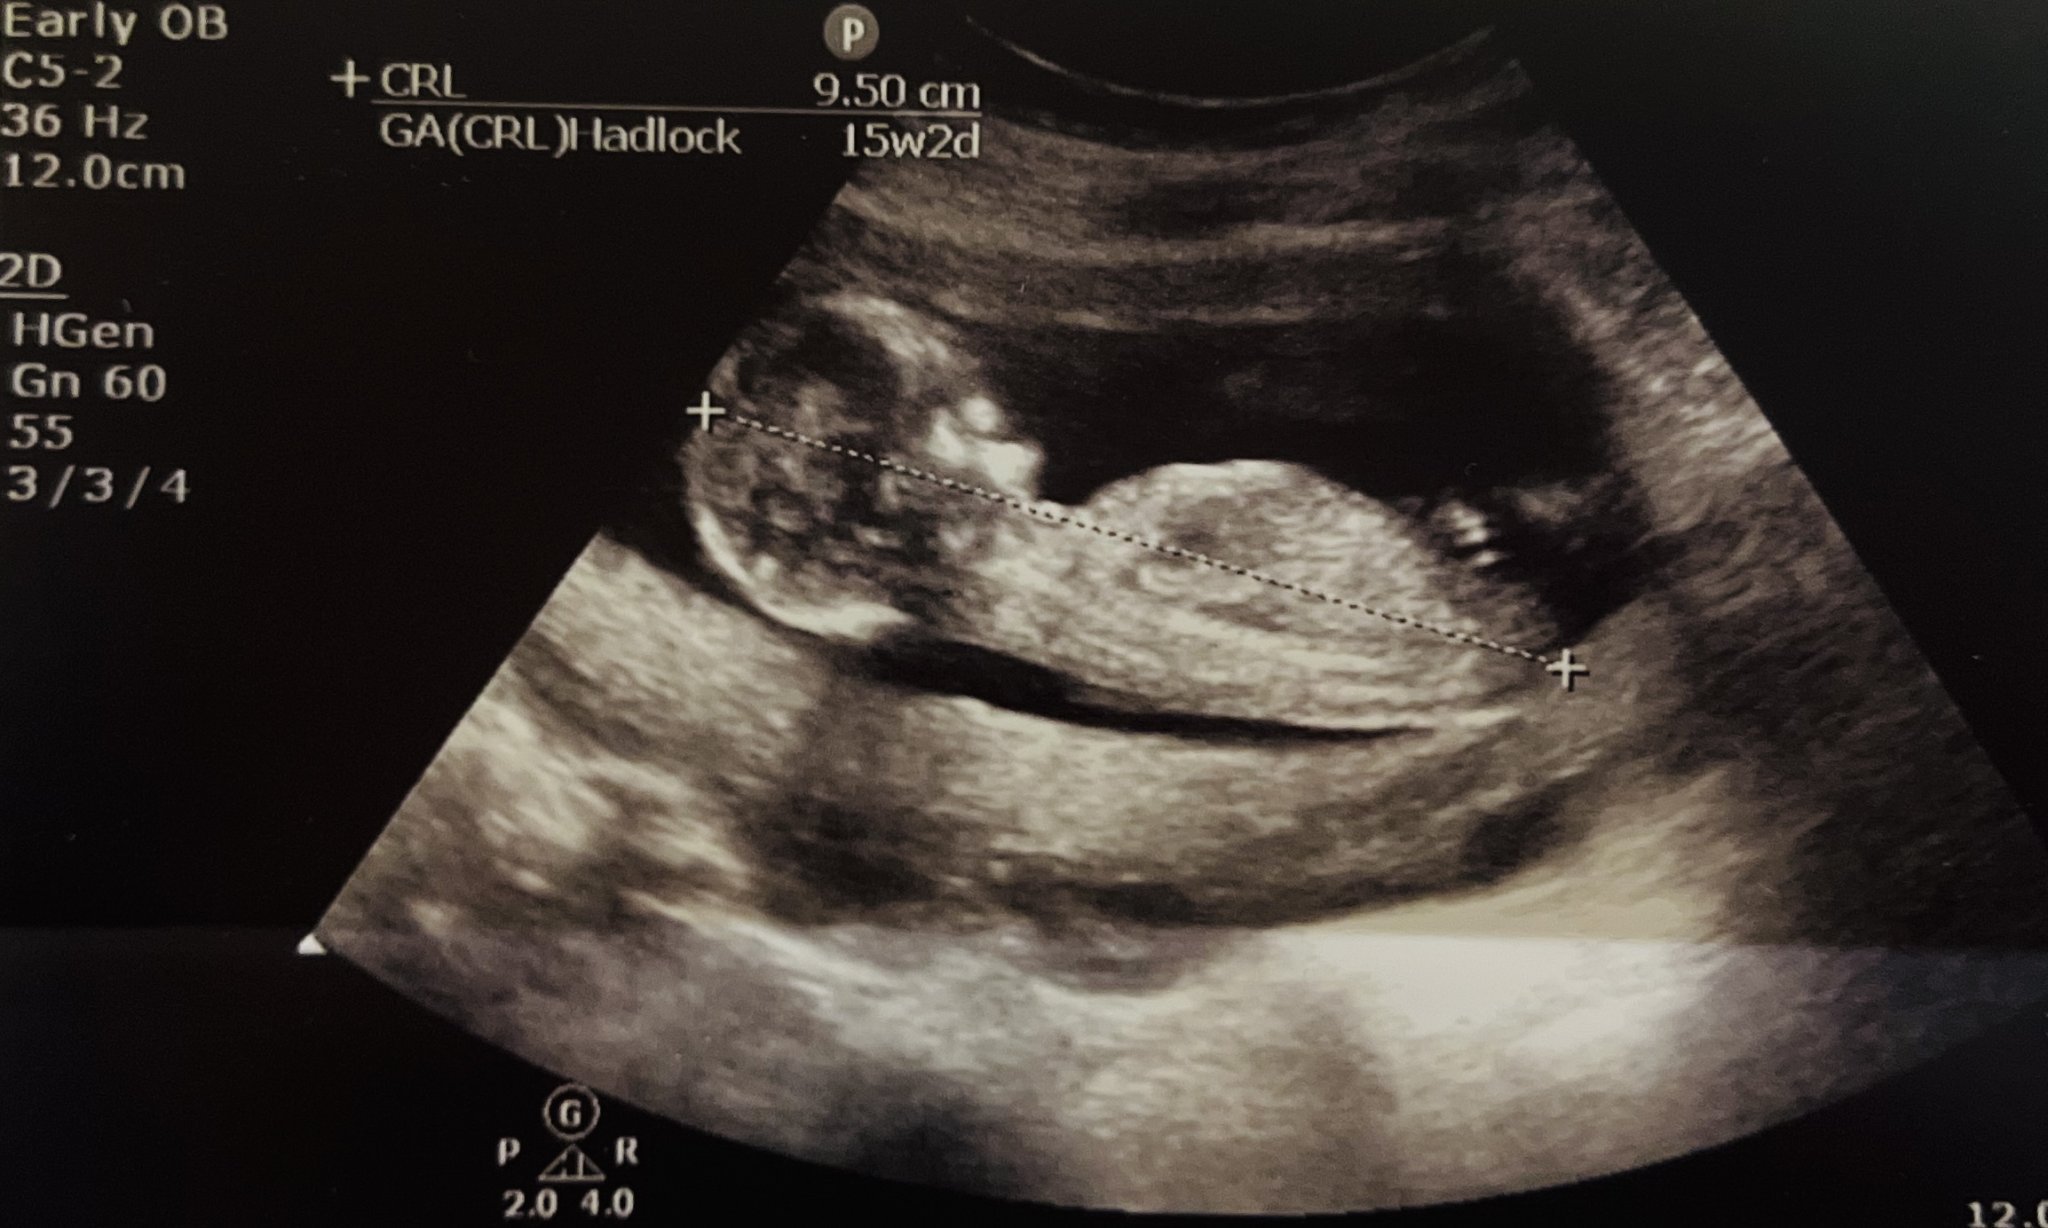

Здравейте момичета , днес бях на преглед в шейново заради болки , супер разочарована съм от преглеждащата лекарка. Но това е друга тема и проблем , който не искам да коментирам в момента … много ме ядоса. Нищо не обяснява, коментира ми кистата която знам че имам и веднага искаше да ме хоспитализира , при отказ от моя страна се държа супер грубо ( груб беше и целия преглед ) , накрая изписа нош-па и това беше. Измери бебчето с една седмица напред , според нея всеки апарат измервал различно …. Сега друго се чудя , според вас момиче или момче ще бъде ?